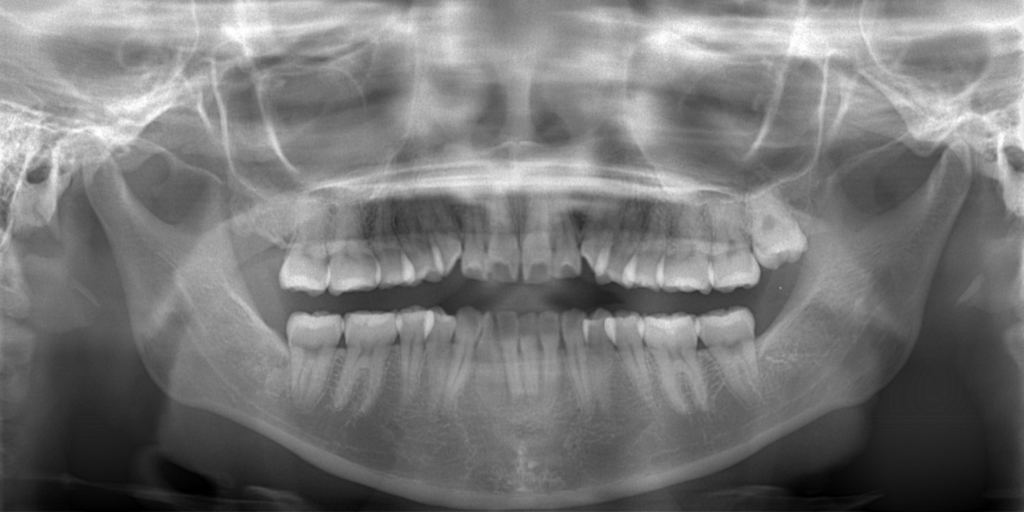

【診断】

#1.歯と顎の不調和による叢生(軽~中等度)

と診断しました。

【抜歯】

上下の左右の奥歯を1本ずつ計4本抜歯(すべて前から4番目の第一小臼歯を抜きました)

左上の埋伏している智歯は治療開始後早期に抜歯します。

ついでに、歯並びの比較です

上段が矯正治療前、下段が矯正治療後